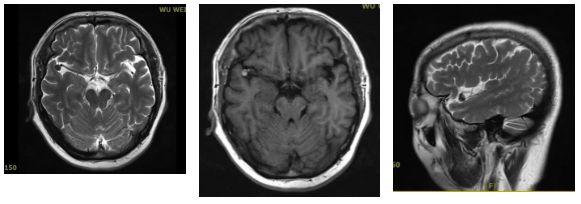

头颅MRI:

右侧大脑中动脉M2起始部异常信号结节,考虑动脉瘤